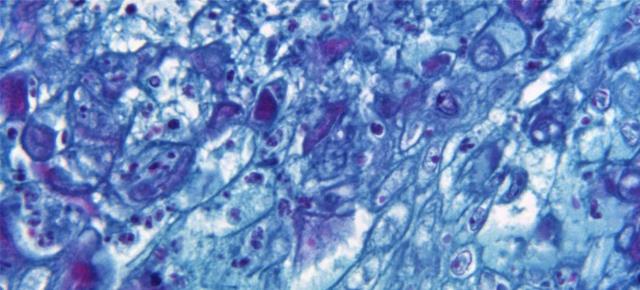

La Organización Mundial de la Salud está preocupada porque la transmisión sostenida de la viruela del mono pueda hacer que el virus llegue a grupos de alto riesgo.

“Me preocupa la transmisión sostenida porque sugeriría que el virus se está estableciendo y podría pasar a los grupos de alto riesgo, incluidos los niños, los inmunodeprimidos y las mujeres embarazadas. Estamos empezando a ver esto con varios niños ya infectados”, dijo el doctor Tedros Adhanom Gebreyesus, el director general de la Organización.

Un experto de la OMS detalló de que Reino Unido ha informado de dos casos en niños, aunque precisó que en esta categoría entran todos los menores de 18 años. Francia y España tienen casos por confirmar. Todos tienen síntomas leves.

«No obstante, es un grupo de edad que realmente nos preocupa, aunque sean [casos] leves, así que tenemos que hacer todo lo posible para controlar este brote a través de las medidas sanitarias existentes», declaró el doctor Abdi Mahamud, coordinador del Equipo de Emergencias.

Por el momento, se han detectado 3413 los casos de viruela del mono en cincuenta países